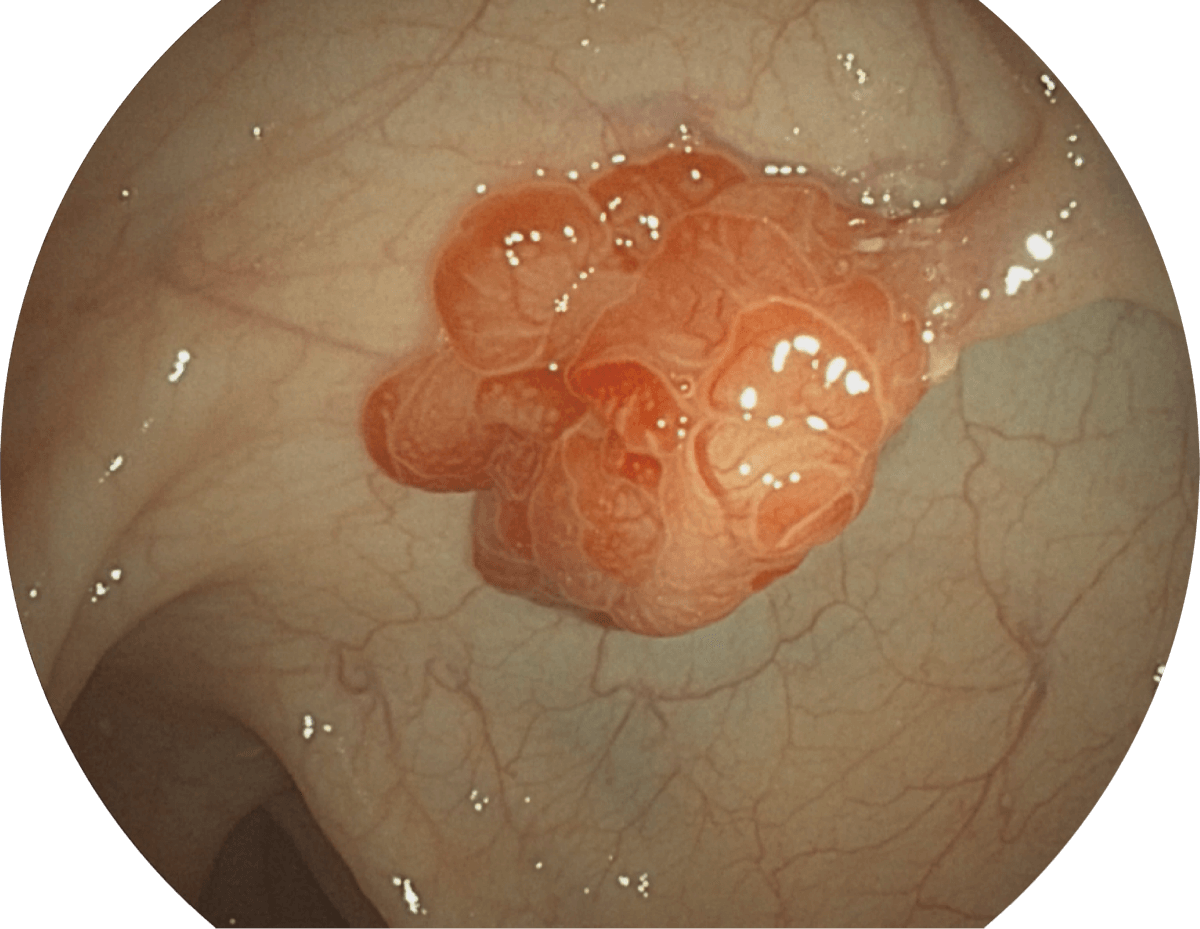

具有聚谱成像技术(SFI)及光电复合染色成像技术(VIST),可完美呈现粘膜细节及病变特征。

WL

1080P视频信号输出,图像清晰。